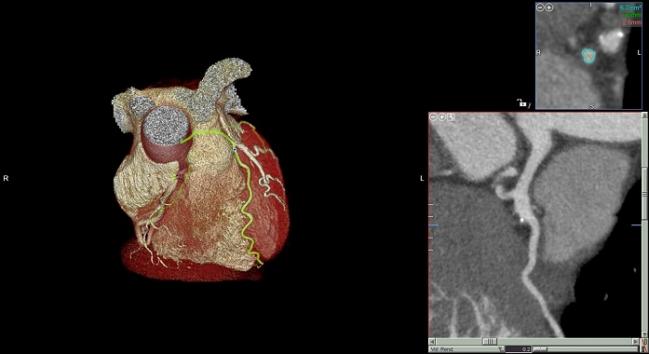

Ct Coronary Angiography Low Dose Ct Scan For The Heart Arteries

3d Angio Tomography Scan Of Lad Heart Collage Stock Photo Image Of Colorful Cardio

The computed tomography pulmonary angiogram (CTPA / CTPE) is a commonly performed diagnostic examination to exclude pulmonary emboli Each radiology department will have a slightly different method for achieving the same outcome, ie adequate enhancement of the pulmonary trunk and its branches. Welcome to University Radiology, the largest Board Certified provider of diagnostic imaging and subspecialty radiology services in NJ We have 21 imaging centers and partner with 8 regional healthcare centers hospitals Imaging services include MRI, Dexa, PETCT, CT scan, Xray, Ultrasound, Mammogram, Health Screenings, and Nuclear Medicine. Coronary CT angiography is the use of computed tomography angiography to assess the coronary arteries of the heart The subject receives an intravenous injection of radiocontrast and then the heart is scanned using a high speed CT scanner, allowing physicians to assess the extent of occlusion in the coronary arteries, usually in order to diagnose coronary artery disease CTA is superior to coronary CT calcium scan in determining the risk of Major Adverse Cardiac Events.

Coronary CT angiography is the use of computed tomography angiography to assess the coronary arteries of the heart The subject receives an intravenous injection of radiocontrast and then the heart is scanned using a high speed CT scanner, allowing physicians to assess the extent of occlusion in the coronary arteries, usually in order to diagnose coronary artery disease CTA is superior to coronary CT calcium scan in determining the risk of Major Adverse Cardiac Events. Angiography is a type of Xray used to check blood vessels Blood vessels do not show clearly on a normal Xray, so a special dye needs to be injected into your blood first This highlights your blood vessels, allowing your doctor to see any problems. Your cardiac calcium scoring can predict your risk of heart attack Find out out your CAC score with a simple imaging scan at UM Medical Center.

CT Angiography is a noninvasive imaging study that helps see fat and calcium deposits that have accumulated in the coronary arteries These deposits, called plaques, can lead to blockages which can cause chest pain, shortness of breath, and/or heart attacks.